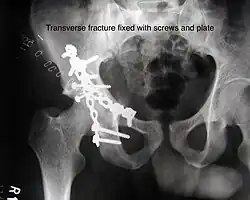

The final management depends on the size of the fragment(s), stability and congruence of the joint. In some cases traction for six to eight weeks may be the only treatment required; however, surgical fixation using screw(s) and plate(s) may be required if the injury is more complex. The latter treatment will be called for if bone fragments do not fall into place, or if they are found in the joint, or if the joint itself is unstable.

Transverse fracture fixed with screws and plate